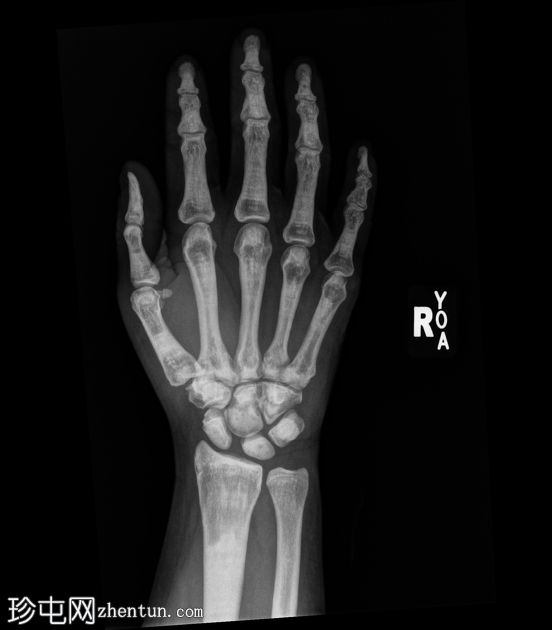

骨硬化症

X线片

正位

弥漫性骨硬化,符合骨硬化症病史。无急性骨折。左髋关节慢性脱位。

弥漫性骨硬化,符合骨硬化症病史。骨中骨征。无急性骨折。

该患者长期患有骨硬化症。虽然骨骼放射密度极高,但比正常骨骼更脆弱,骨折风险较高:该患者发生右股骨骨折(未显示)。骨髓功能也受损,患者可能出现髓外造血。